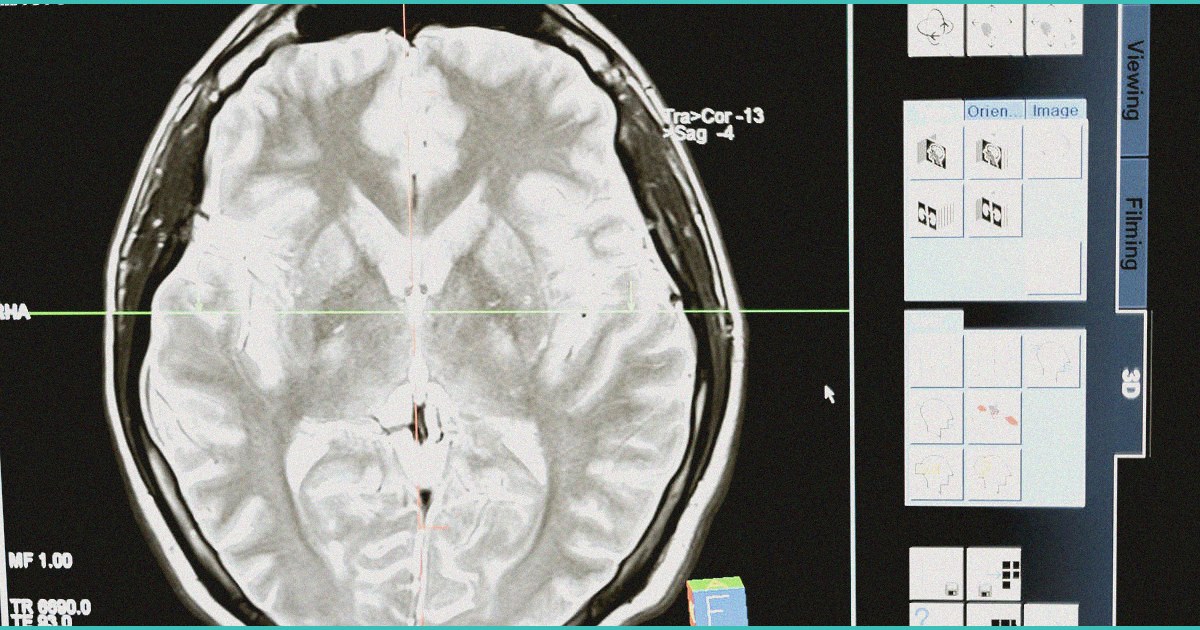

A longitudinal study examining lifetime cannabis use patterns found no significant association between cannabis consumption and cognitive decline or dementia risk in older adults, challenging previous assumptions about cannabis-related neurotoxicity in aging populations. The research tracked cognitive outcomes across extended follow-up periods, controlling for confounding variables such as alcohol use, education, and cardiovascular health. These findings suggest that moderate to occasional lifetime cannabis use does not appear to accelerate age-related cognitive deterioration or increase dementia susceptibility, which may inform clinical counseling regarding cannabis safety in older patient populations. However, the study does not address heavy or daily use patterns, acute cognitive effects, or the impact of high-potency cannabis products now prevalent in legal markets. Clinicians should recognize that while this evidence reduces concern about cannabis hastening cognitive aging, individual patient factors including drug interactions, fall risk, and specific medical contraindications remain important considerations in cannabis recommendations. Patients with concerns about cognitive health and cannabis use can be reassured that current evidence does not support accelerated cognitive decline from typical lifetime use patterns.

🧠 A recent observational study reported no association between lifetime cannabis use and cognitive decline or dementia risk in older adults, findings that may reassure some patients but warrant cautious interpretation given the study’s limitations. The cross-sectional design and reliance on self-reported cannabis exposure create substantial confounding risks, as cannabis users may differ systematically from non-users in unmeasured health behaviors, socioeconomic status, or baseline cognitive reserve. Existing longitudinal evidence remains mixed, particularly regarding heavy or early-life use, chronic exposure duration, and THC-to-CBD ratios, leaving important questions unresolved about dose and timing of exposure. Rather than using this single study to counsel patients that cannabis is cognitively safe, clinicians should acknowledge the genuine uncertainty, discuss individual risk factors such as age of initiation and frequency of use, and note that older adults may face particular vulnerability to cannabis-related cognitive or psychomotor effects regardless